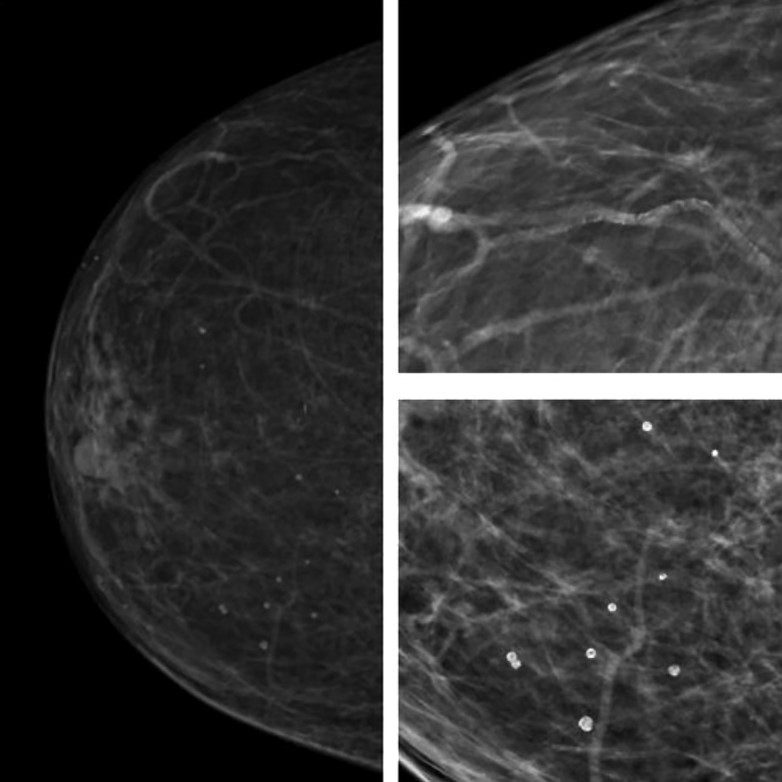

Внутрикожные кальцинаты локализованы преимущественно в дерме и являются результатом обызвествления протоков сальных желез. Чаще всего локализуются группами, имеют кольцевидную или точечную форму (Рис.3).

Множественные рассеянные точечные микрокальцинаты характерны для склерозирующего аденоза – доброкачественного состояния, при котором отмечается увеличение долек молочных желез и их дисторция окружающей фиброзной тканью [13] (Рис.7).